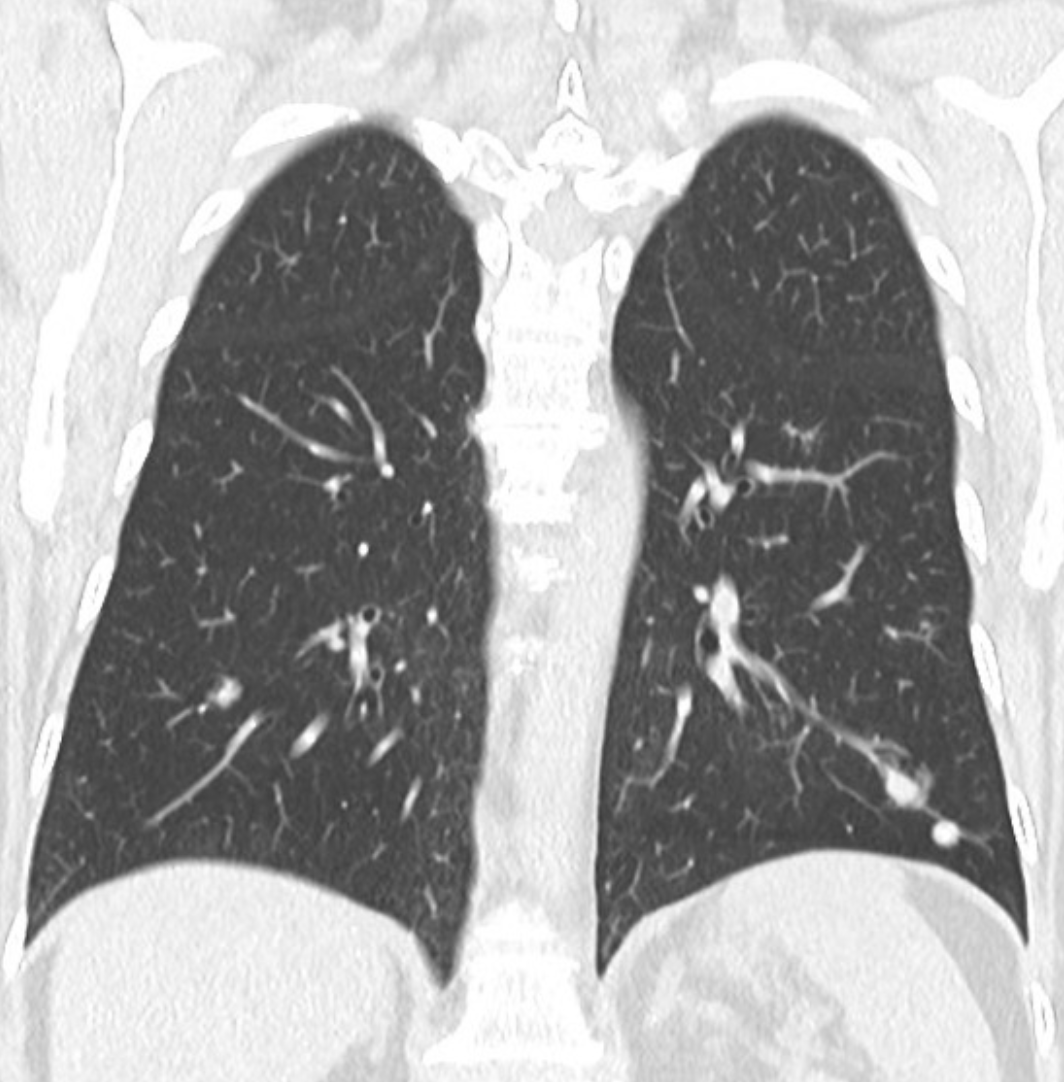

What is the pathology of this condtion?

ACUTE INTERSTITIAL PNEUMONIA (AIP) * Diffuse alveolar damange * 1st picture: EXUDATIVE PHASE * hyaline membranes and alveolar infiltration by LYMPHOCYTES * 2nd picture: 1 year later * ORGANISING PHASE * alveolar wall thickening * fibrosis * traciton bronchiectasis